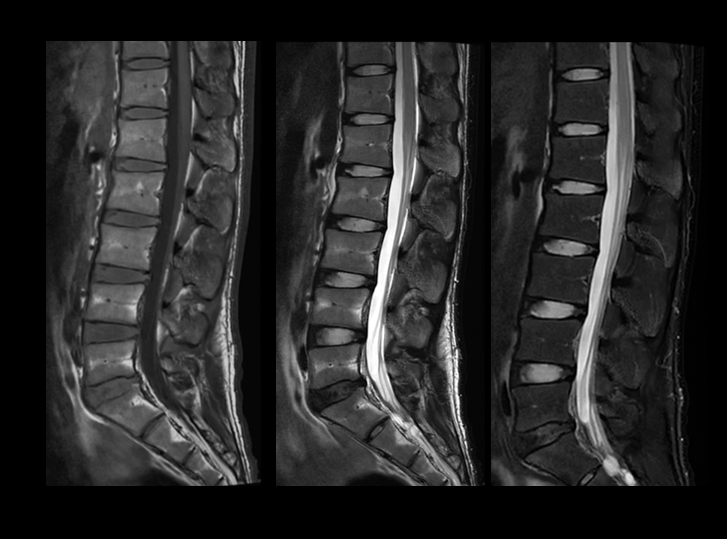

高分辨腰椎成像